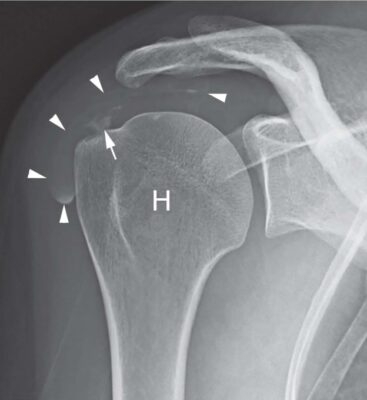

X quang

Với bệnh viêm gân vôi hóa chóp xoay, X quang thường quy có thể phát hiện vôi hóa ở các mô mềm xung quanh xương cánh tay và khoang dưới mỏm cùng vai, từ đó xác định nghi ngờ lâm sàng. X quang cũng có thể phát hiện sự hiện diện của vôi hóa ở những bệnh nhân thực hiện chụp x quang vì những lý do khác.

Nhìn chung, kích thước của cặn vôi hóa không thay đổi đáng kể theo thời gian. Một số tác giả đã phân loại cặn canxi dựa trên kích thước, hình thái hoặc hình ảnh X quang.

- Gartner và Heyer đã phân loại bệnh viêm gân hóa chóp xoay thành:

- loại I, giới hạn rõ, vôi hóa dày đặc, thì hình thành;

- loại II: đường viền mềm/đặc hoặc sắc nét/trong suốt; và

- loại III; hình ảnh mờ và đục, không có ranh giới rõ ràng, giai đoạn hấp thu (Hình 3).